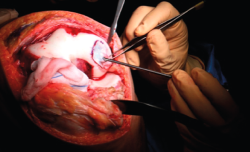

1. A paramedial joint incision is made, with luxation of the knee and access to the lesion (Figure 6).

2. The damaged cartilage is cleaned using curettes, with debridement of the defect, and the lesion is left with healthy and exposed subchondral bone (Figure 7).

8. The membrane is placed in the lesion and the margins of the former are sutured to the healthy cartilage with Vicryl® 5/0 (Figures 11 and 12).